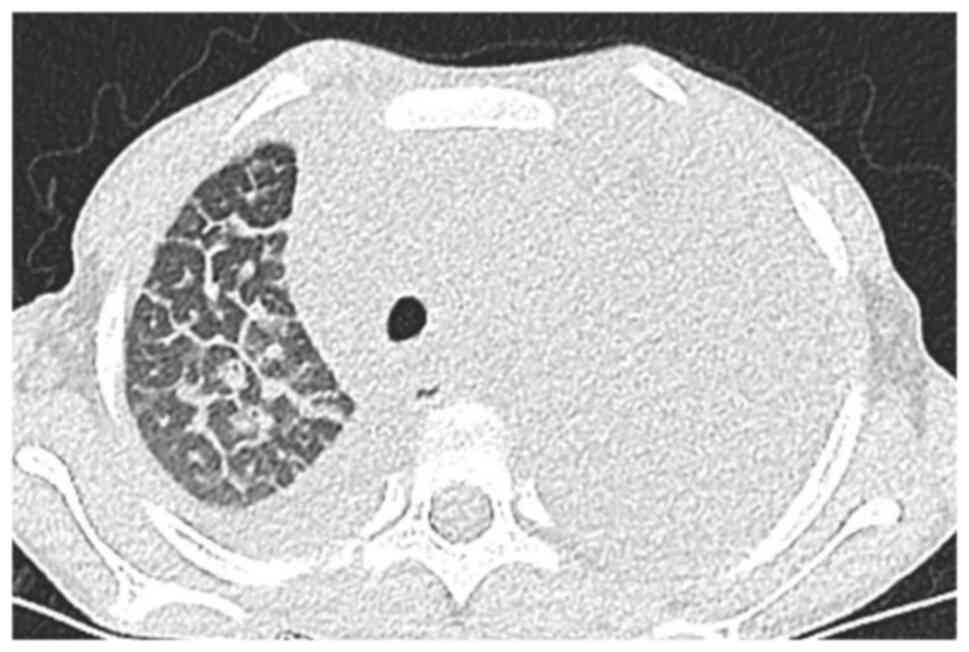

Laboratory examinations revealed severe microcytic hypochromic anemia, with hemoglobin value of 80 g/l. T-SPOT showed no abnormality. Blood and pleural effusion cultures were negative. The pleural fluid test suggested chylothorax. Contrast-enhanced chest CT (Figs. 1 and 2) showed multiple lymph nodes in bilateral cervical roots and mediastinum, which were fused into clusters, and the trachea and mediastinal great vessels were surrounded. Furthermore, there was multiple thickening of interlobular septa in the right lung, multiple inflammations in both lungs and atelectasis in the left lung, and massive pleural effusion on the left side. Positron emission tomography (PET)-CT showed soft tissue thickening around the trachea, blood vessels, and thyroid gland in the lower neck and the mediastinum, especially in the anterior and superior mediastinum. The pulmonary interlobular septum was significantly thickened, and the bronchial vascular bundle was thickened, accompanied by multiple patchy shadows of increased density and consolidation. The pleural effusion of the child was chylous (Fig. 3). Biopsy of the mediastinal mass revealed patchy, small lymphocytes with few thymus corpuscles. The tumor tissue was fissured and had a sparse reticular structure (Fig. 4). Immunohistochemistry results revealed the following: D2-40 (+), CD31 (+), Ki67 (1%+), SALL4 (-), SOX-10 (-), SMA (-), TDT (-), CD5 (-), CD117 (-), PLAP (-), AFP (-), HMB45 (-) and tissue changes consistent with the vascular origin of the tumor, inclined to lymphangioma.

Figure 1

Multiple thickening of interlobular septa in the right lung.